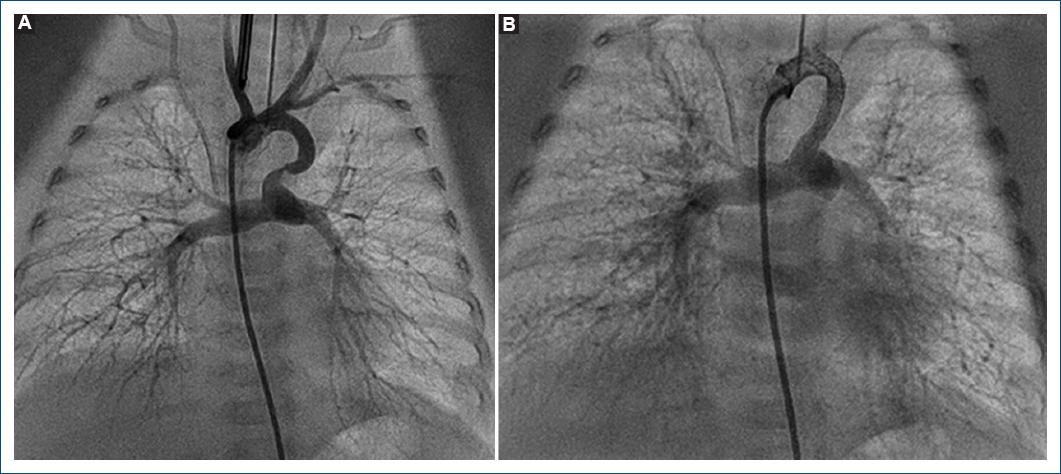

Los procedimientos fueron llevados a cabo en el servicio de hemodinamia del Hospital Garrahan, formado por cuatro hemodinamistas con años de experiencia en el tratamiento de cardiopatías congénitas de pacientes recién nacidos. La distribución de los casos fue similar entre estos. Todos los pacientes fueron planteados para el procedimiento luego de realizar el diagnóstico inicial con ecocardiograma. En algunos casos fue necesario realizar angio-TC con contraste para definir adecuadamente la morfología del conducto, y en unos pocos casos el cateterismo diagnóstico inicial se utilizó para plantear la posibilidad de implantar un stent ductal. En la actualidad se encuentra protocolizada la realización de angio-TC en aquellos pacientes en quienes se plantee la colocación de un stent en el conducto arterioso para definir con mayor certeza la morfología ductal. En los casos que correspondía se suspendió el goteo de prostaglandinas 12 horas antes para favorecer la constricción pulmonar. Para el procedimiento, todos los pacientes requirieron anestesia general con asistencia respiratoria mecánica. En la mayoría de los casos el acceso vascular utilizado fue tanto arterial como venoso, y los introductores oscilaron entre 3 y 5 Fr. En cuatro pacientes el acceso arterial fue carotídeo por el origen del conducto arterioso desde el tronco braquiocefálico. Se utilizaron stents coronarios no farmacológicos con diámetros entre 3.5 y 4.5 mm y de longitud variable. En siete casos fue necesario el implante de dos stents para mantener la permeabilidad del conducto arterioso (Figs. 1 y 2). Al finalizar el procedimiento se efectuó angiografía de control para certificar el buen funcionamiento del stent y su permeabilidad, y luego, con una saturación acorde al modelo hemodinámico, se finalizó el procedimiento y los pacientes pasaron a la unidad de cuidados intensivos (Fig. 3). Posterior al procedimiento se encuentra protocolizado mantener anticoagulación con heparina por 48 horas y luego iniciar antiagregación con ácido acetilsalicílico.

Figura 2 A: angiografía que evidencia origen del conducto arterioso en el tronco braquiocefálico izquierdo en un paciente con tetralogía de Fallot y arco aórtico derecho. Se evidencia algo de tortuosidad y constricción en el tercio proximal a la arteria pulmonar. B: angiografía tras la angioplastia con colocación de dos stents.

Figura 3 Angiografía tras la angioplastia con un stent en un conducto arterioso originado en el arco transverso en un paciente con atresia pulmonar con comunicación interventricular.